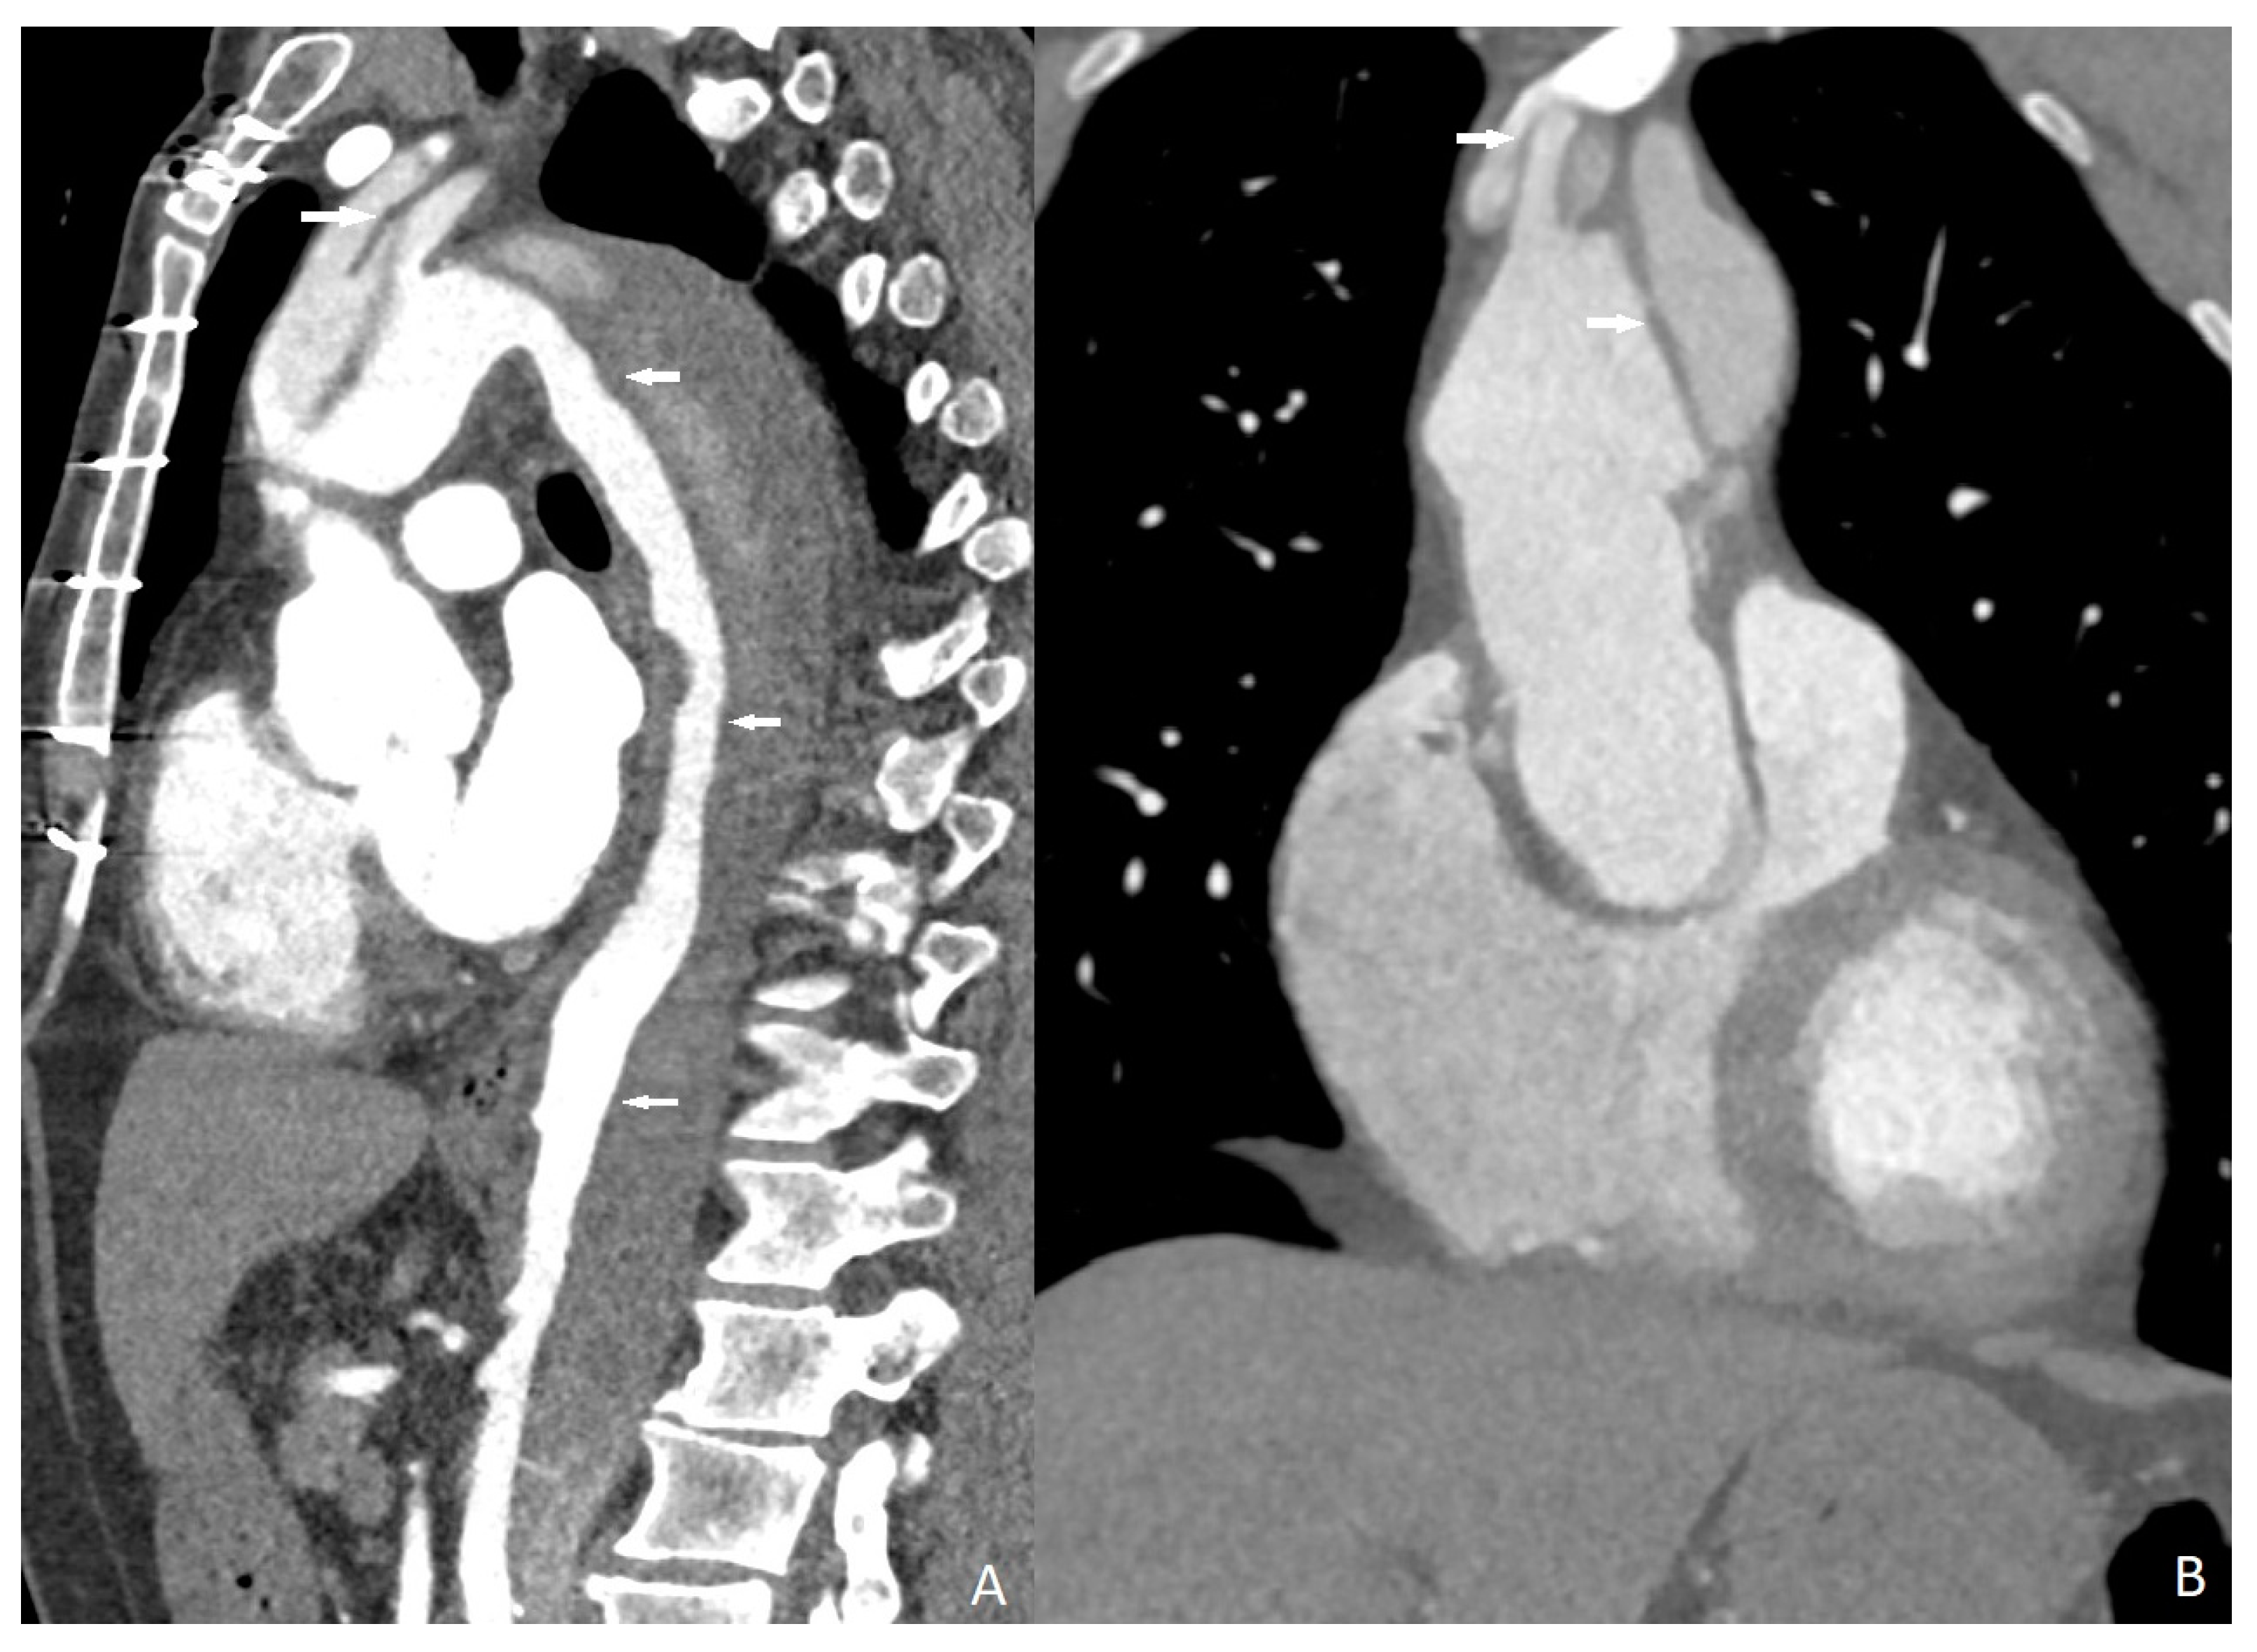

Three cases were overestimated as having obstructive coronary artery disease, and one case was underestimated as having negative obstructive coronary artery disease; all of the erroneous results were caused by calcified aterosclerotic plaques. Sensitivity, specificity, and positive and negative predictive values of quadruple-rule-out CT for obstructive coronary artery disease were 96.1% (95% confidence interval [CI] 93–99%), 93.4% (95%CI 90–99%), 89.2% (95%CI 86–94%), and 97.7% (95%CI 94–100%), respectively (Figure 2). Cohen’s coefficient of variation (ĸ value) for the presence of obstructive CAD was 0.78 (substantial).

Figure 2.

Obstructive coronary artery disease in the midportion of the left anterior descending artery ((A) arrow, (B) marking) and in the proximal portion of the right coronary artery ((C) arrow, (D) marking).